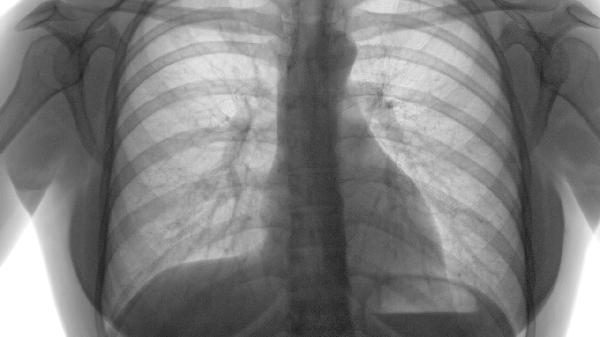

肺气肿主要表现为肺泡壁破坏导致气体交换障碍,通过肺功能检查可评估FEV1第一秒用力呼气容积下降程度。轻度肺气肿患者FEV1占预计值≥80%,而重度患者可能低于30%,需长期氧疗或呼吸康复训练延缓进展。

肺气肿可能由长期吸烟、空气污染、职业粉尘接触、遗传性α-1抗胰蛋白酶缺乏等原因引起,需通过肺功能检查、胸部影像学...